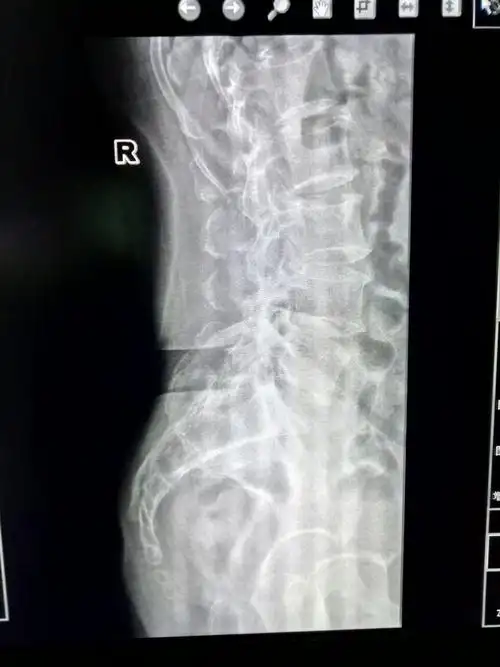

(笑哭)原来以为脊椎是一条弧线弯下去,没想到尾椎骨那里是这样长的